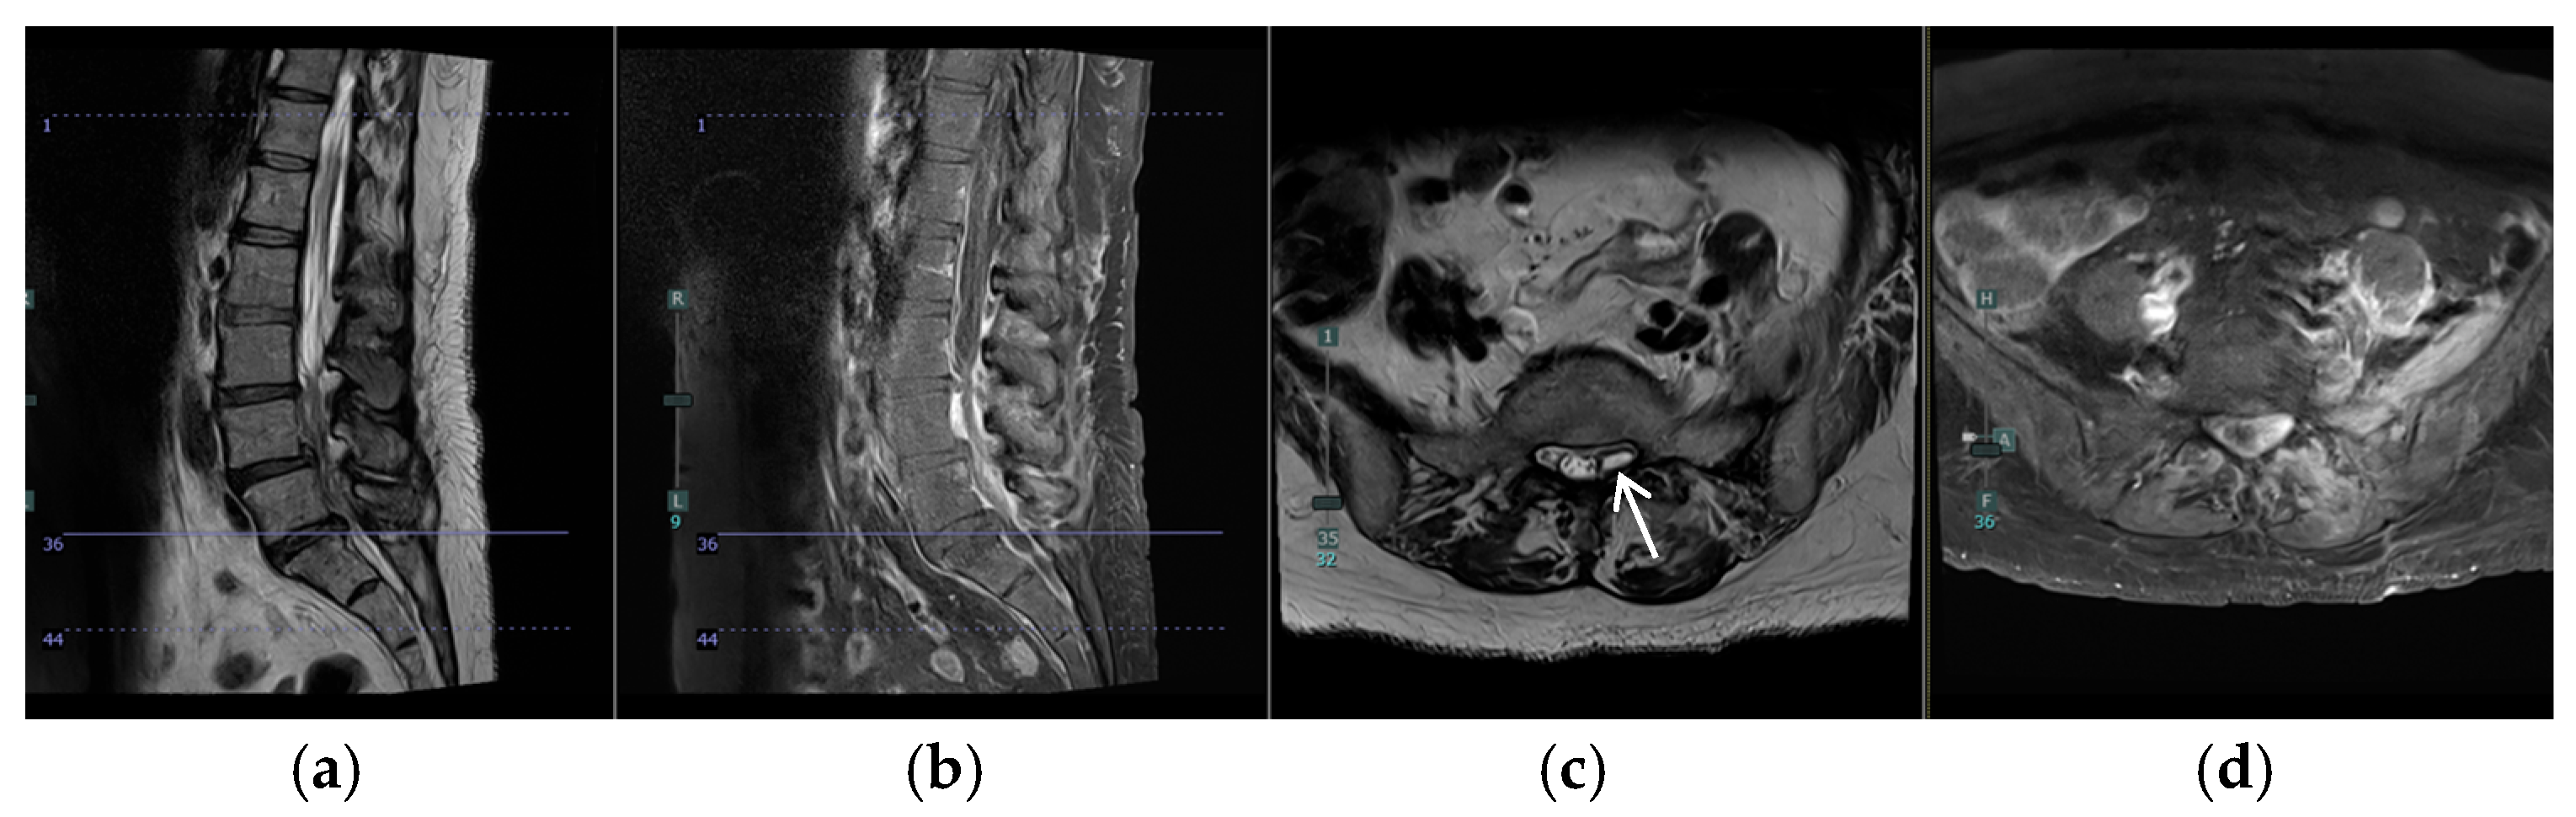

A 57-year-old female with a past medical history of osteoarthritis and prediabetes presented with three days of worsening back and left leg pain. Her initial examination revealed significant tenderness in the lumbar region and decreased sensation in the left S1 distribution. She had preserved motor function but reported progressive difficulty with ambulation due to pain. Two months prior, she had undergone a T8–T10 laminectomy for excision and drainage of a thoracic epidural abscess and left piriformis abscess aspiration, followed by a six-week course of intravenous antibiotics (Figure 1a–c). Imaging at presentation demonstrated a resolving thoracic infection but revealed worsening diffuse lumbar facet infection and a left-sided L5/S1 epidural abscess causing cauda equina and S1 root compression (Figure 1d–f and Figure 2).

Figure 2. Preoperative MRI of the lumbar spine showing left-sided L5/S1 epidural abscess causing cauda equina and S1 root compression (white arrow). (a) Sagittal T2, (b) Sagittal T1 with contrast, (c) Axial T2 at S1, and (d) Axial T1 with contrast L5/S1.